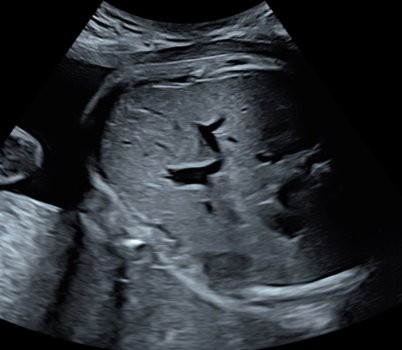

Kuva 2: 3D ultraäänikuva

Kuva 3: Sikiön maksa ultraäänikuvassa.

Tutkimuksessamme selvitämme, onko sikiön maksan ultraäänikuvien tekstuurista mahdollista havaita viitteitä sikiön insuliininerityksestä. Menetelmä voisi tarjota nopean ja turvallisen keinon arvioida sikiön aineenvaihduntaa ja mahdollistaa aiempaa tarkemman raskausdiabeteksen hoidon.